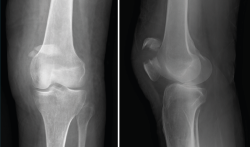

3. Artrosis

La gonartrosis es la causa más frecuente del dolor de rodilla después de los 50 años. En la radiografía se observa una reducción de la interlínea femorotibial o femoropatelar, y una osteofitosis marginal (Figura 6).

Figura 6. Radiografías anteroposterior y lateral de rodilla: osteofitos en compartimentos femorotibial y femoropatelar.